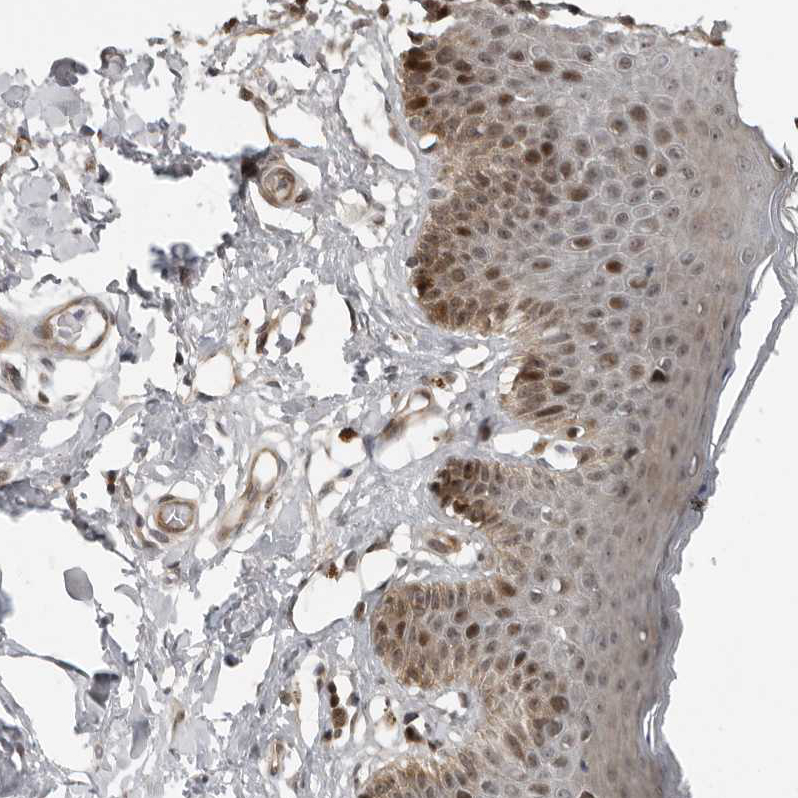

Immunohistochemical staining of human skin shows moderate nuclear positivity in squamous epithelial cells.